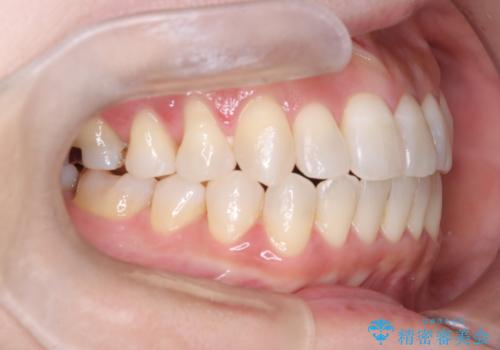

【開咬】笑った時の見た目を改善したい。

- 重度の開咬でしたがインビザラインで適切に治療計画を立て、きれいに仕上がりました。

インビザラインは開咬の治療に向いています。